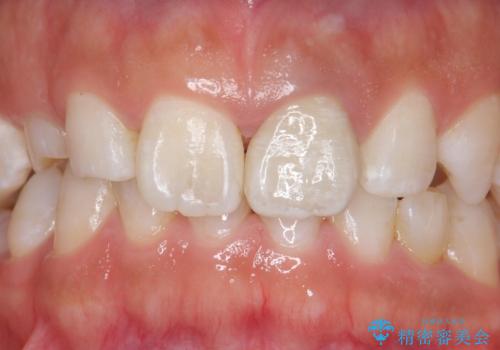

モザイク模様の前歯 オールセラミッククラウンで整った印象に